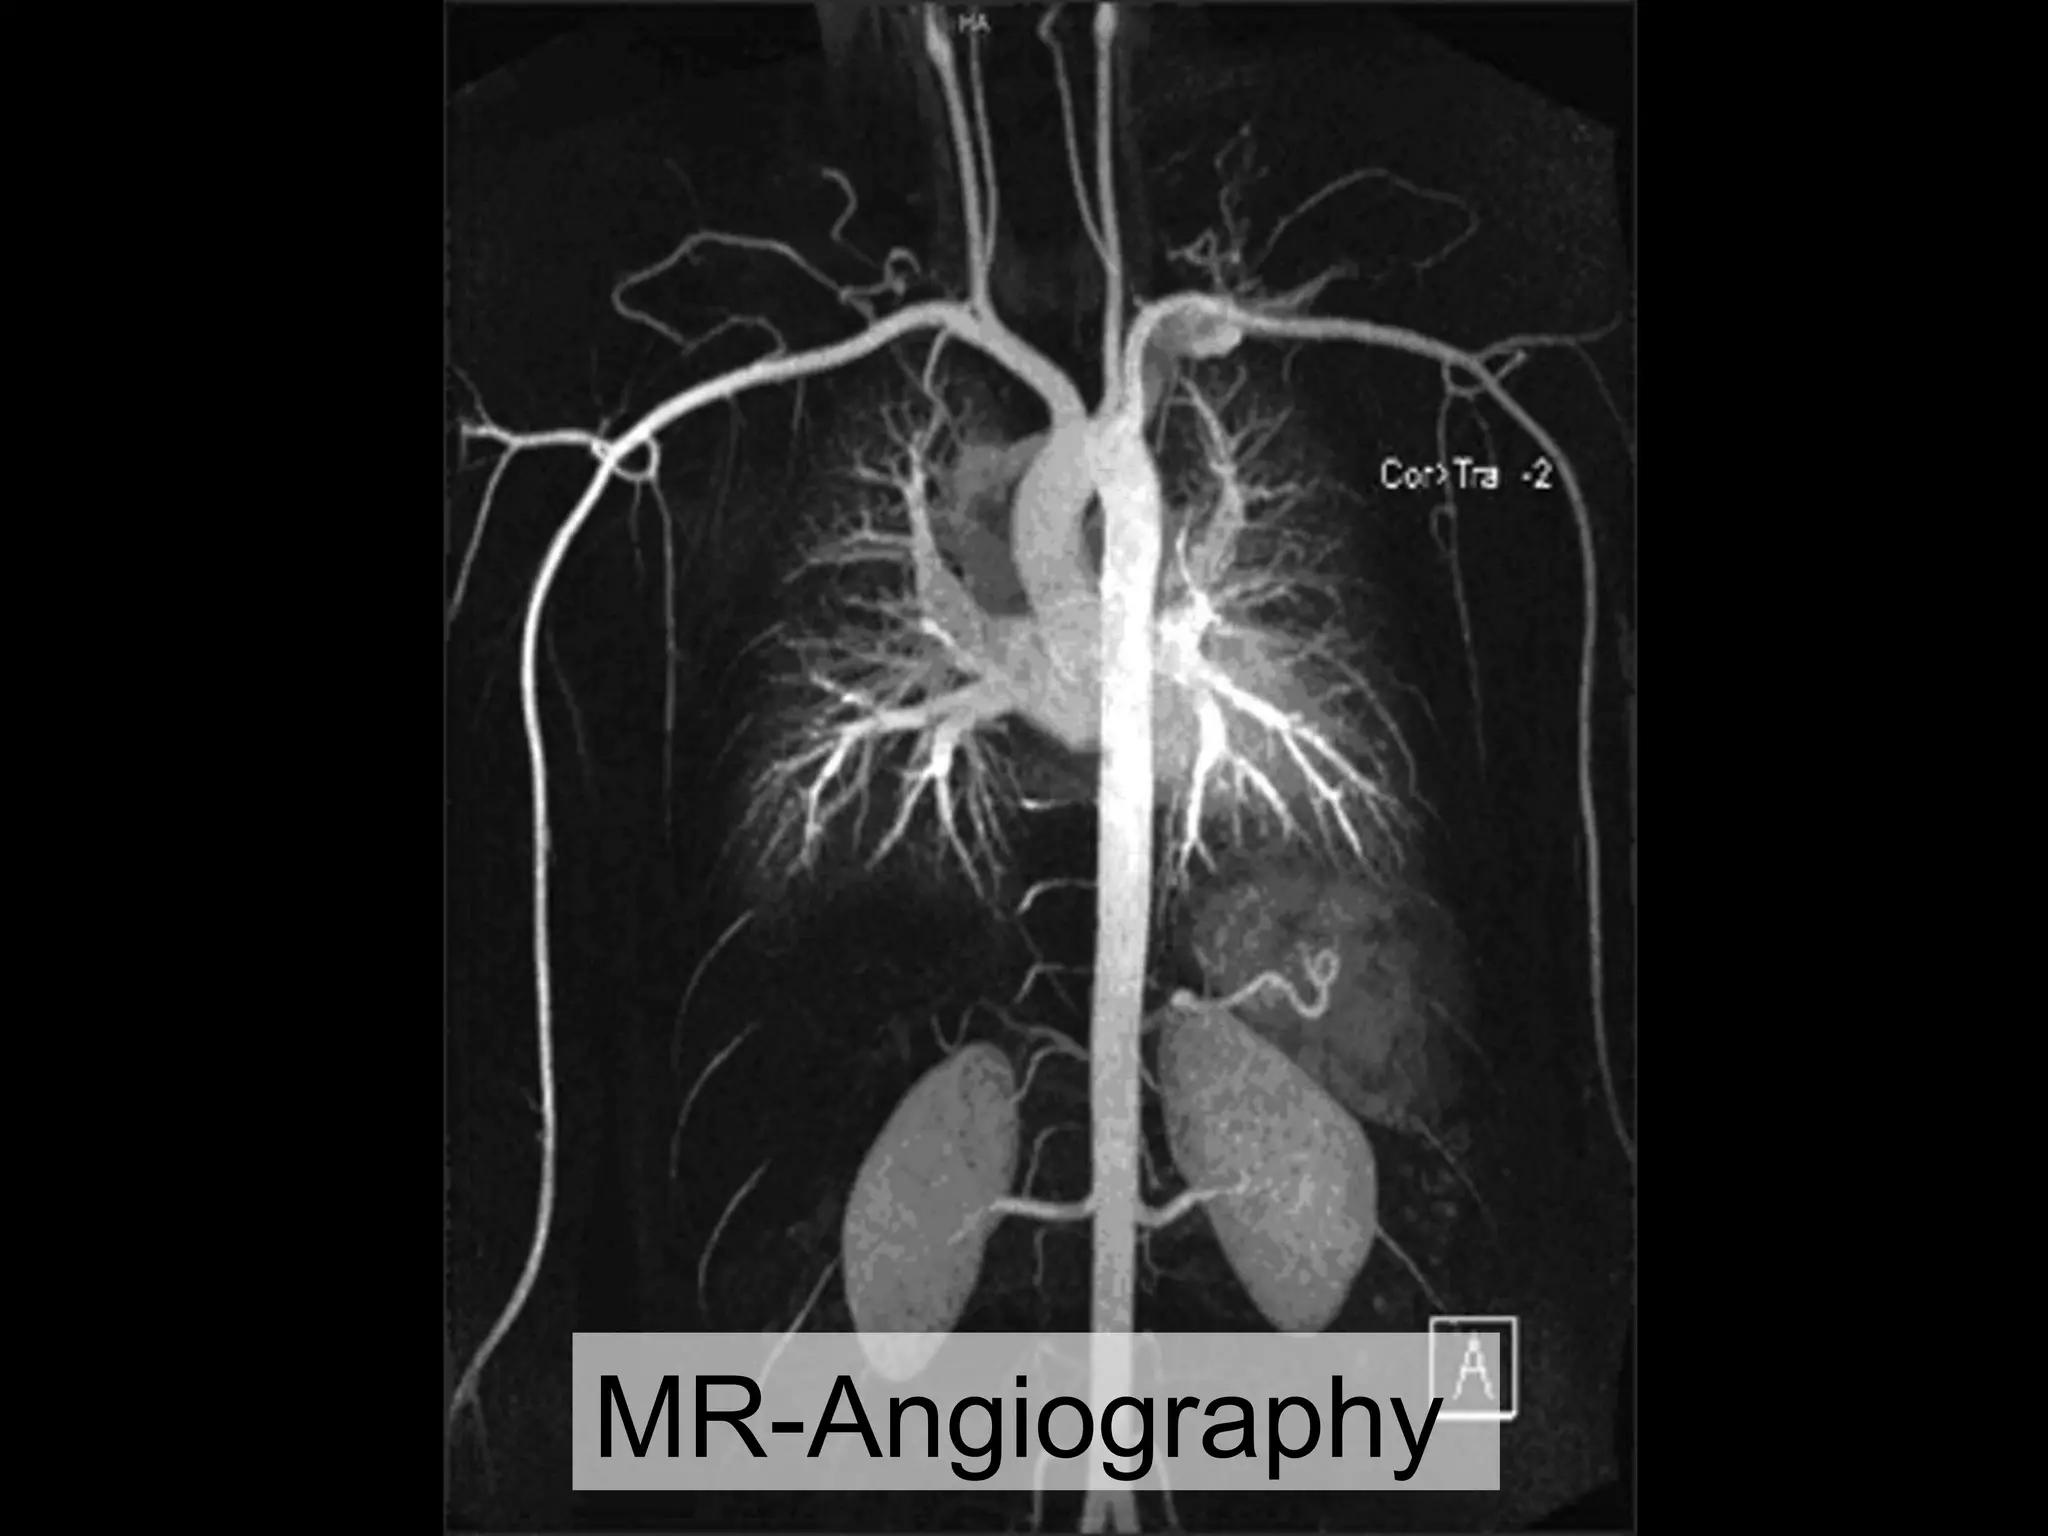

• Computed Tomography Angiography (CTA) and Magnetic Resonance Angiography (MRA): Advanced imaging techniques that provide detailed images of the arteries.